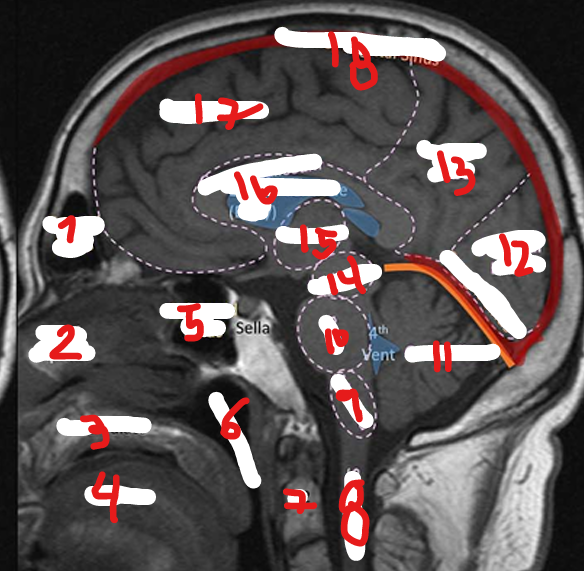

FRONTAL LOBE

1

<p>1</p>

New cards

PARIETAL LOBE

2

8

TEMPORAL LOBE

<p>3</p>

9

4

<p>4</p>

10

OCCIPITAL LOBE

5

<p>5</p>

CEREBRUM

6

12

CEREBELLUM

<p>7</p>

FRONTAL SINUS

17

<p>17</p>

MEDULLA

<p>9</p>

PONS

<p>10</p>

11

<p>11</p>

<p>12</p>

13

<p>13</p>

MIDBRAIN

14

<p>14</p>

THALAMUS

15

<p>15</p>

CORPUS CALLOSUM

16

<p>16</p>

SUPERIOR SAGITAL SINUS

18

<p>18</p>